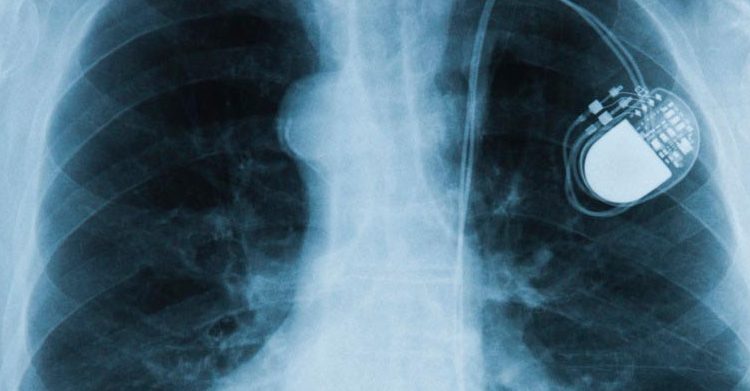

Santo Domingo. – La Agencia del Medicamento de Estados Unidos (FDA por sus siglas en inglés) advirtió que algunos dispositivos como ciertos teléfonos y relojes inteligentes, tienen imanes de alta intensidad de campo capaces de afectar temporalmente el funcionamiento normal de dispositivos médicos electrónicos implantados como marcapasos y desfibriladores implantables.

En este sentido, la FDA aconsejó a los pacientes con dichos dispositivos a que tomen precauciones como: mantener el dispositivo inteligente a seis pulgadas de distancia de los aparatos médicos implantados y abstenerse de llevar los teléfonos o relojes inteligentes en un bolsillo cercano al marcapasos o desfibrilador.

La agencia detalló: »Creemos que el riesgo para los pacientes es bajo y la agencia no tiene conocimiento de ningún evento adverso asociado con este problema en este momento. Sin embargo, se espera que la cantidad de productos electrónicos de consumo con imanes potentes aumente con el tiempo. Por lo tanto, recomendamos a las personas con dispositivos médicos implantados que hablen con su médico para asegurarse y conozcan las técnicas adecuadas para un uso seguro».